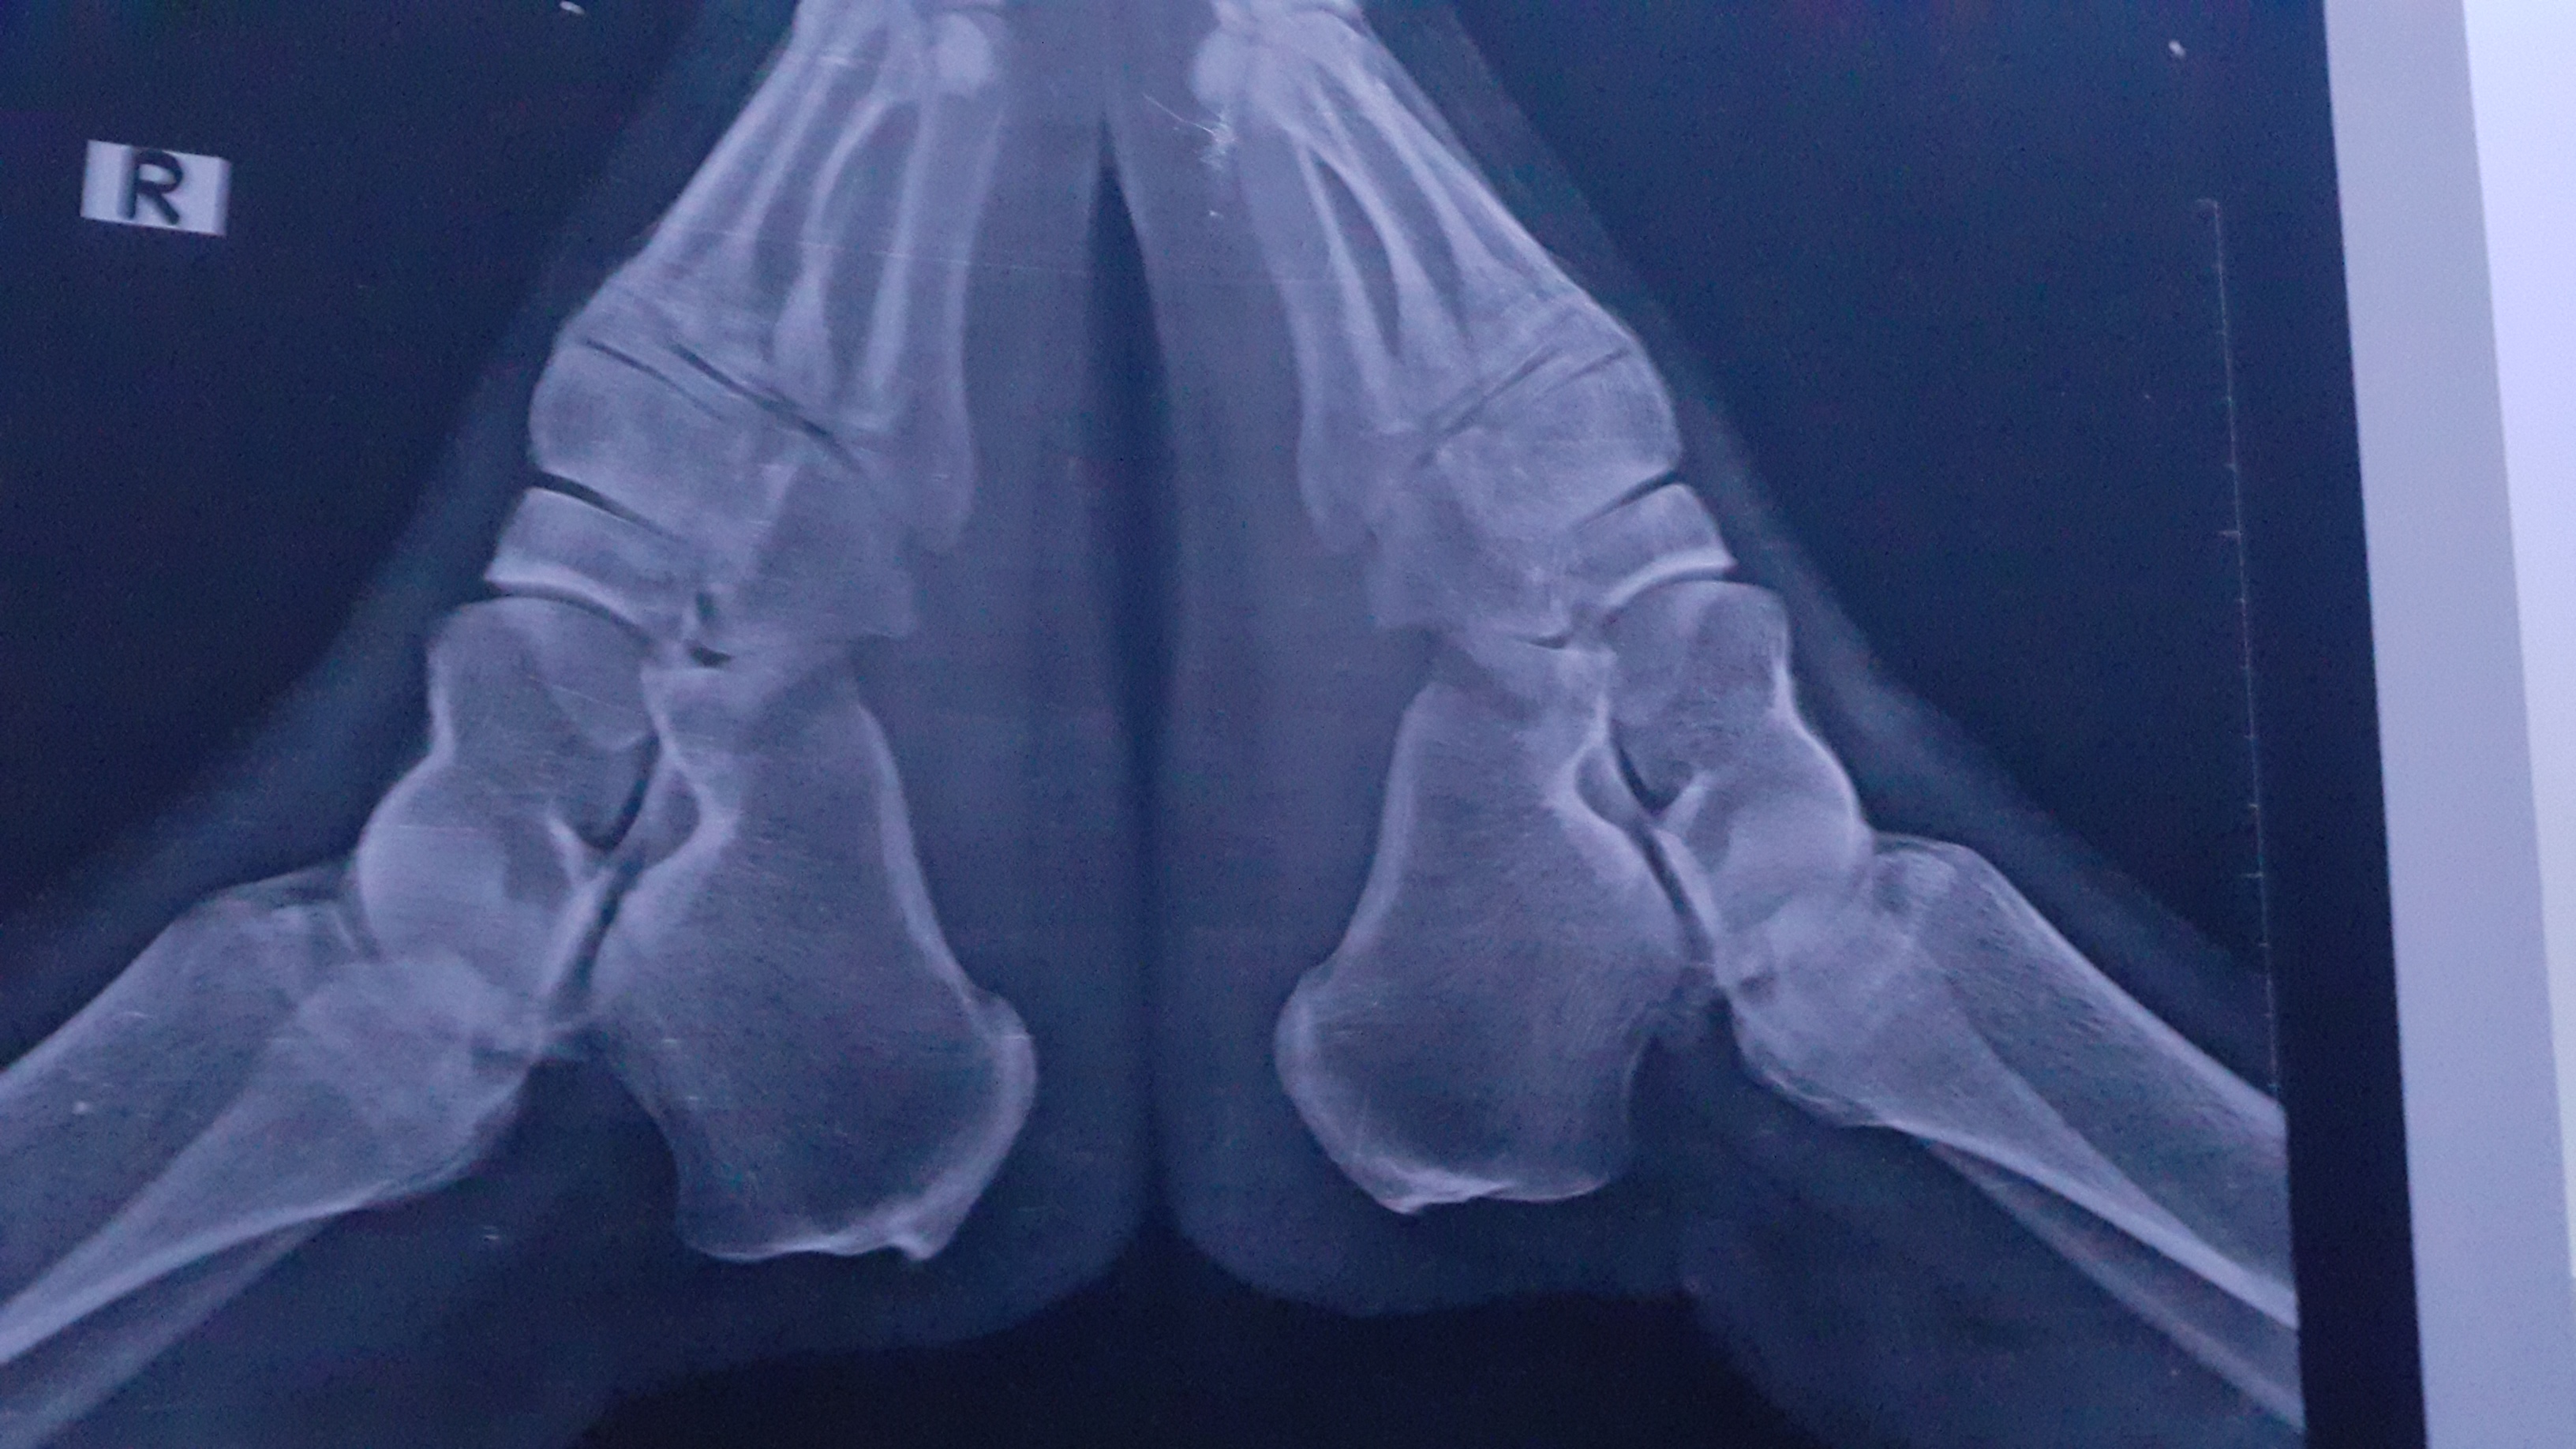

أشعر بالم في اسفل الضهر عند الانحناء لوقت قليل مثل الوضوء و الم في كعب القدم عند الوقوف لوقت قصير ووجع نشر حتي فوق الركبة مع أقل مجهود وصوت في مفاصل الركبتين والكتفين

الفحص السريري مهم عليك مراجعة طبيب روماتيزم لاجراء اللازم من تصوير وتحليل للدم ومن ضمنه نسبة الالتهاب ووظائف الاعضاء للاهميه CBC ESR CRP ALT Creatinine وكذلك تحاليل اخرى لمعرفة نوع الالتهاب وذلك حسب الفحص السريري وممكن رنين للمفصل الحرقفي وممكن تحليل HLA B27 حسب مايراه طبيب الروماتيزم 0 2026-03-10T09:26:43+00:00 2026-03-10T09:26:43+00:00

الفحص السريري مهم عليك مراجعة طبيب روماتيزم لاجراء اللازم من تصوير وتحليل للدم ومن ضمنه نسبة الالتهاب ووظائف الاعضاء للاهميه CBC ESR CRP ALT Creatinine وكذلك تحاليل اخرى لمعرفة نوع الالتهاب وذلك حسب الفحص السريري وممكن رنين للمفصل الحرقفي وممكن تحليل HLA B27 حسب مايراه طبيب الروماتيزم